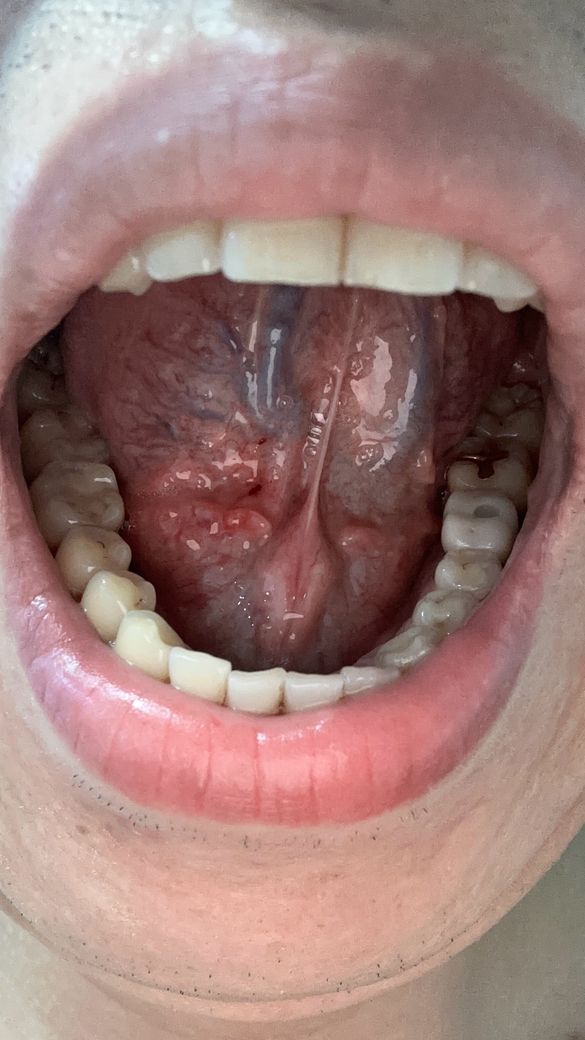

양치하다가 칫솔로 눌렀는데 아파지고 빨개진거같아요

빨갛게 된부분이 있는것같고 그래서 이거 병원가봐야되는지 그냥 냅둬도 괜찮음지 궁금해요 어떻게하는게 좋을까요?? 병원은 무슨과인가요?

• 2번 째 사진